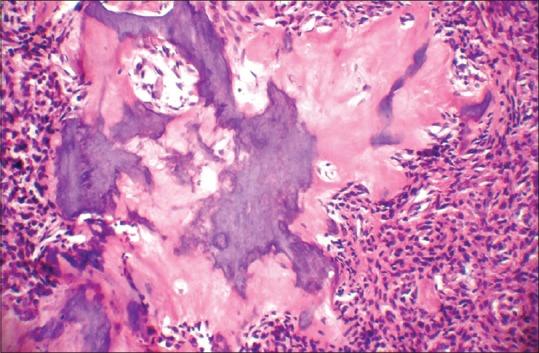

Routray Samapika, Mohanty Neeta, Panda Swagatika, Sahoo Sujit Ranjan

Department of Oral Pathology and Microbiology, Institute of Dental Sciences, Siksha'O' Anusandhan University, Ghatikia, Bhubaneswar, Orissa, India.

J Oral Maxillofac Pathol. 2015 May-Aug;19(2):260-2. doi: 10.4103/0973-029X.164546.